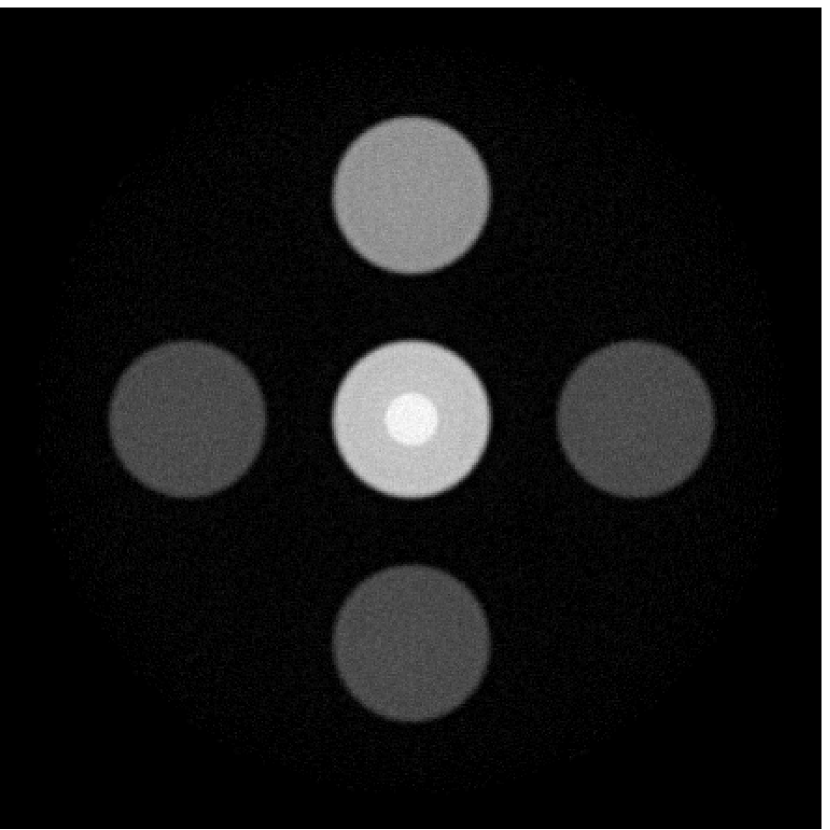

VI-D Results: Needle phantom

Figure 11 displays images of the needle phantom reconstructed by use of the simple backprojection method [BM2003]. Figures 12 and 13 display the images reconstructed by use of the conventional iterative method and VP algorithm, respectively.

Figures 12 and 13 show that the width of the needle in the reconstructed image increases as the regularization parameter increases for both the conventional iterative method and the VP algorithm. The images reconstructed by use of the VP algorithm appear to have a reduced noise level compared to the images reconstructed by the backprojection and conventional iterative methods, regardless of the choice of the regularization parameter values. The profile plots corresponding to these three methods are shown in Figure 14. Since the image of the coefficient vector and the EIR are recoverable only up to a multiplicative constant, every profile was normalized for comparison. These plots demonstrate that the image reconstructed by use of the VP algorithm possessed a more uniform background than those obtained by the backprojection and the conventional iterative methods.